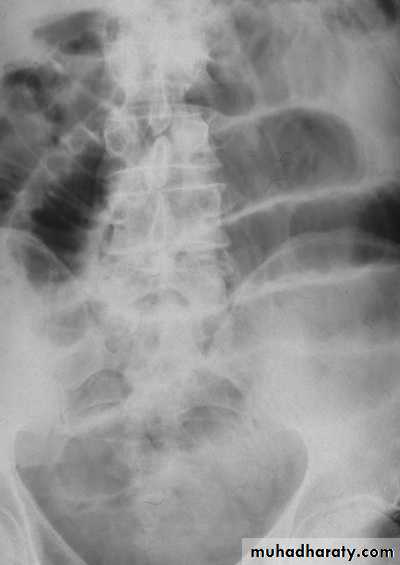

Investigation

Supine abdominal X-ray shows dilated small bowel

May be normal if no air fluid interfaces

Valvulae coniventes differentiate small from large intestine

Erect abdominal film rarely provided additional information